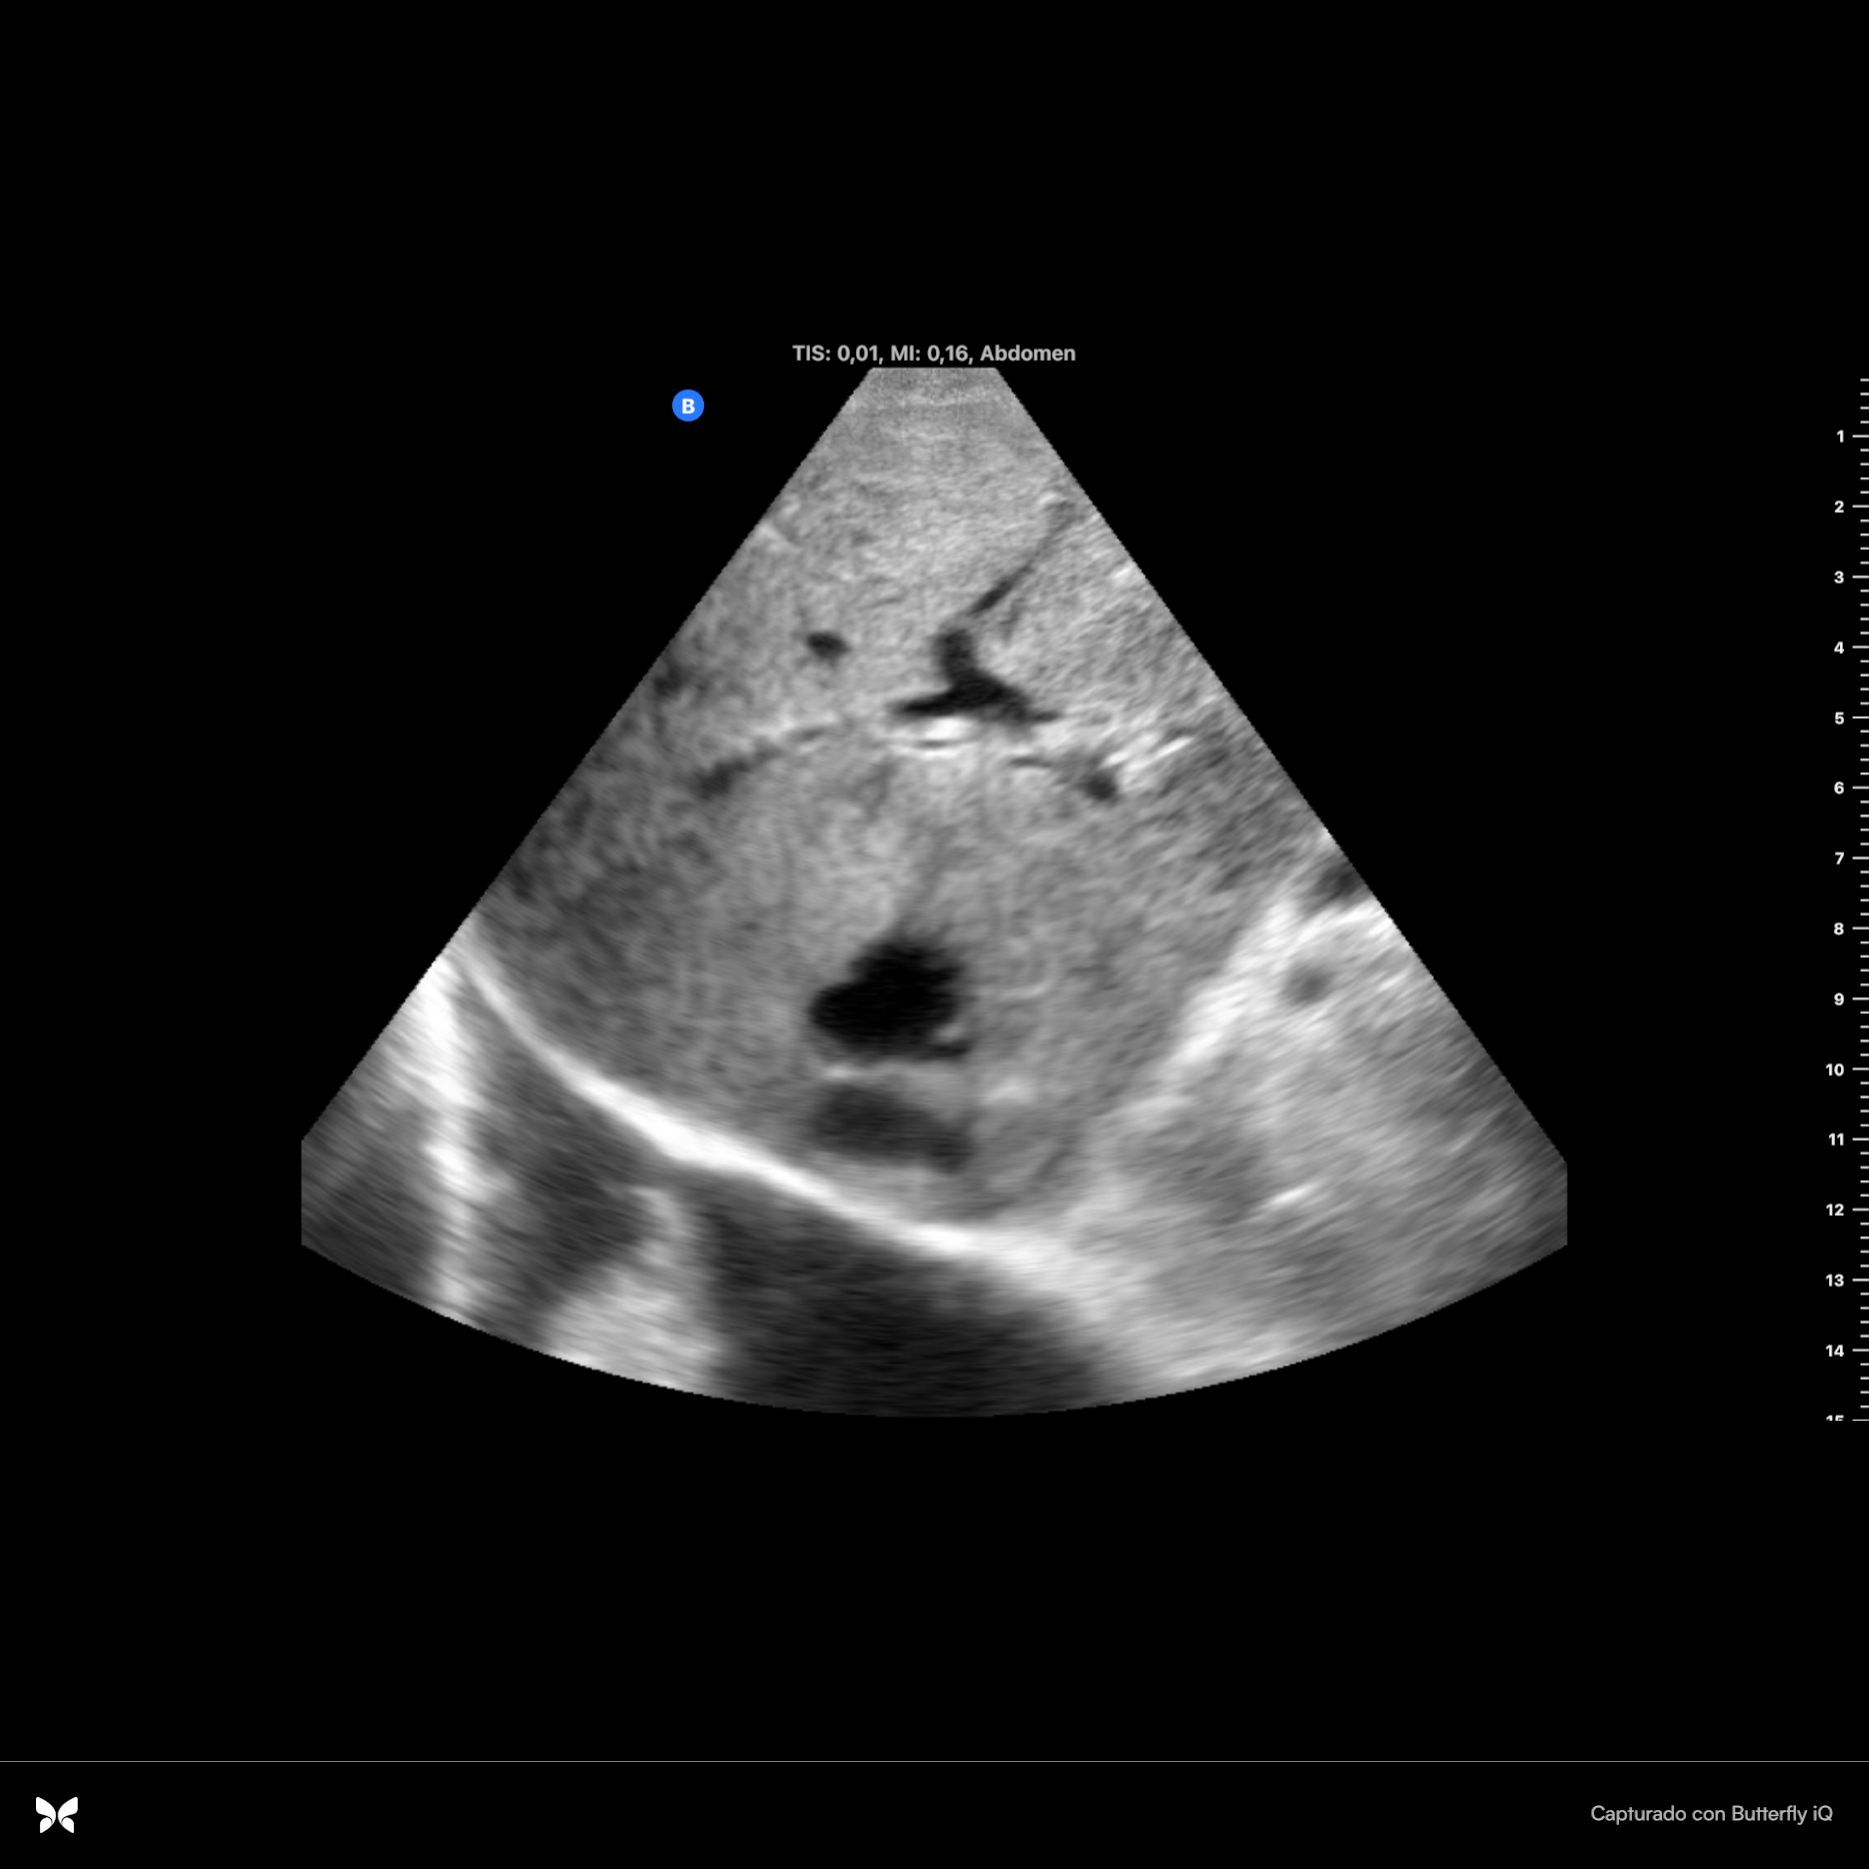

Se observan dos imágenes hiperecoicas en infundíbulo de vesícula que dejan sombra acústica posterior, una de ellas de 2 cm x 0.94 cm con aumento de grosor de vasos suprahepáticas. Parénquima hepático sin alteraciones. Se observa espacio anecoico superior al diafragma. Resto sin hallazgos.